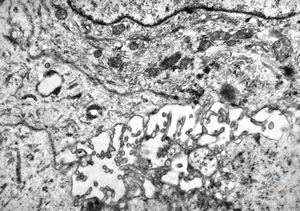

M,50y. | Pneumocystis carinii - lung